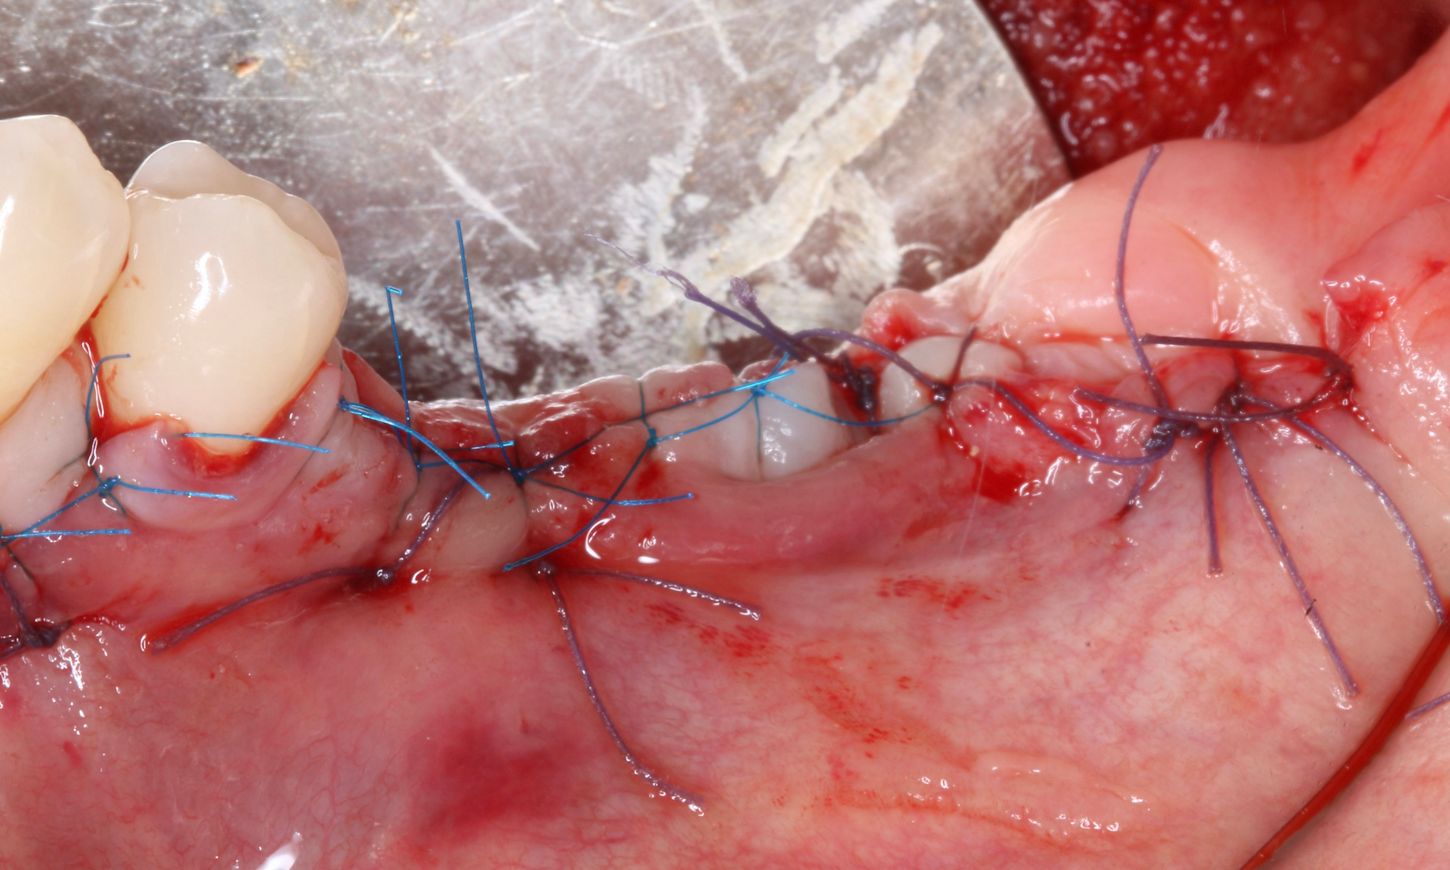

Suturing was performed with 4/0 vicryl and 6/0 prolene, using interrupted sutures to facilitate primary intention wound healing, while the implant remained without the prosthetic crown for 6 months (Fig. 13). After this period of submerged healing, the reinstallation of the suprastructures was planned.